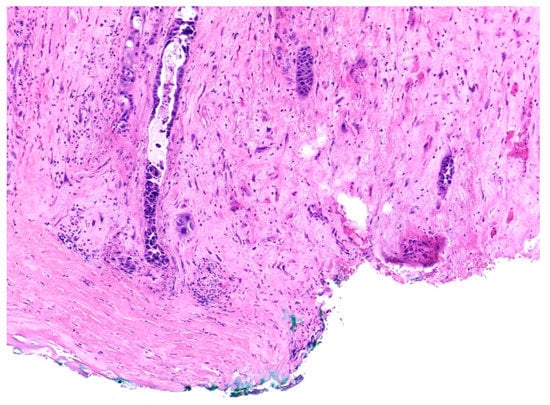

Similar changes can be observed in recurrent/persistent postradiation laryngeal SCCs. Figure 1 illustrates a postradiation recurrent SCC of the vocal cord. The tumor shows no connection with the surface epithelium and consists of cords and a small island of tumor cells within a fibrotic stroma. Although the significance of these findings for the biology of the tumor remains to be fully determined, they nevertheless have an impact on the evaluation of resection margins (Figure 2), as well as on the interpretation of histopathologic findings in biopsies, where neoplastic cells may be difficult to identify in small superficial samples, or if they are set within necrosis or fibrosis (Figure 3). In comparison, postsurgical recurrences of laryngeal SCC consist of irregular infiltrative tumor islands, but necrosis, acellular fibrosis with collagenization, inflammation, and the characteristic damage to vessels are usually absent (Figure 4).

Figure 2. Recurrent squamous cell carcinoma of the vocal cord following radiotherapy. The histologic section shows the deep margin of a specimen of vocal cord resection, inked in green. The tumor consists of small, separated nests of tumor cells and it is thus impossible to assess the margin status with certainty.